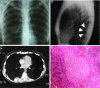

A calcified mass